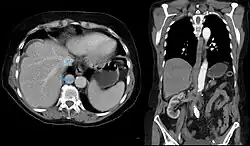

Die Azygoskontinuität der Vena cava inferior gehört zu den angeborenen Fehlanlagen des venösen Abstroms aus der unteren Körperhälfte. Die Vena cava inferior ist nicht durchgängig vorhanden, sondern es fehlt das Segment zwischen der Leber und den Nieren. Die Lebervenen drainieren wie bei der normalen Anatomie über ein kurzes hepatisches Segment nahezu direkt in den rechten Vorhof. Die Nierenvenen münden jedoch mit dem infrarenalen Segment der Vena cava inferior in die Vena azygos, die aufgrund des vermehrten Blutflusses deutlich weiter als normal ist. Diese mündet dann nach normalem Verlauf in die Vena cava superior. Es gibt eine Reihe von Variationen mit jeweils unterschiedlich ausgebildeten Gefäßabschnitten.[1]